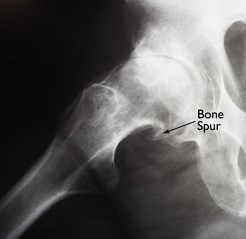

This x-ray shows a large bone spur that has developed on the ball of an arthritic hip.